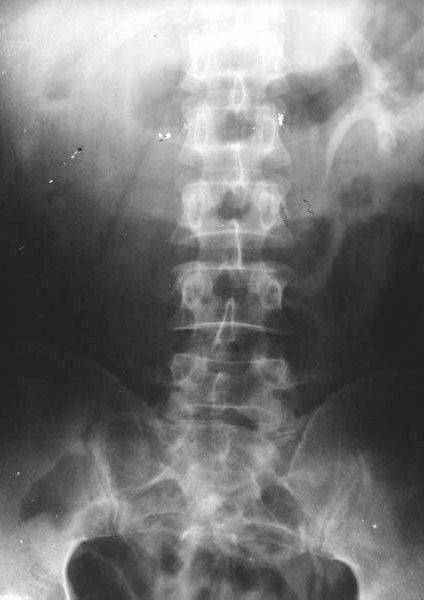

照片名称:胸椎压缩性骨折